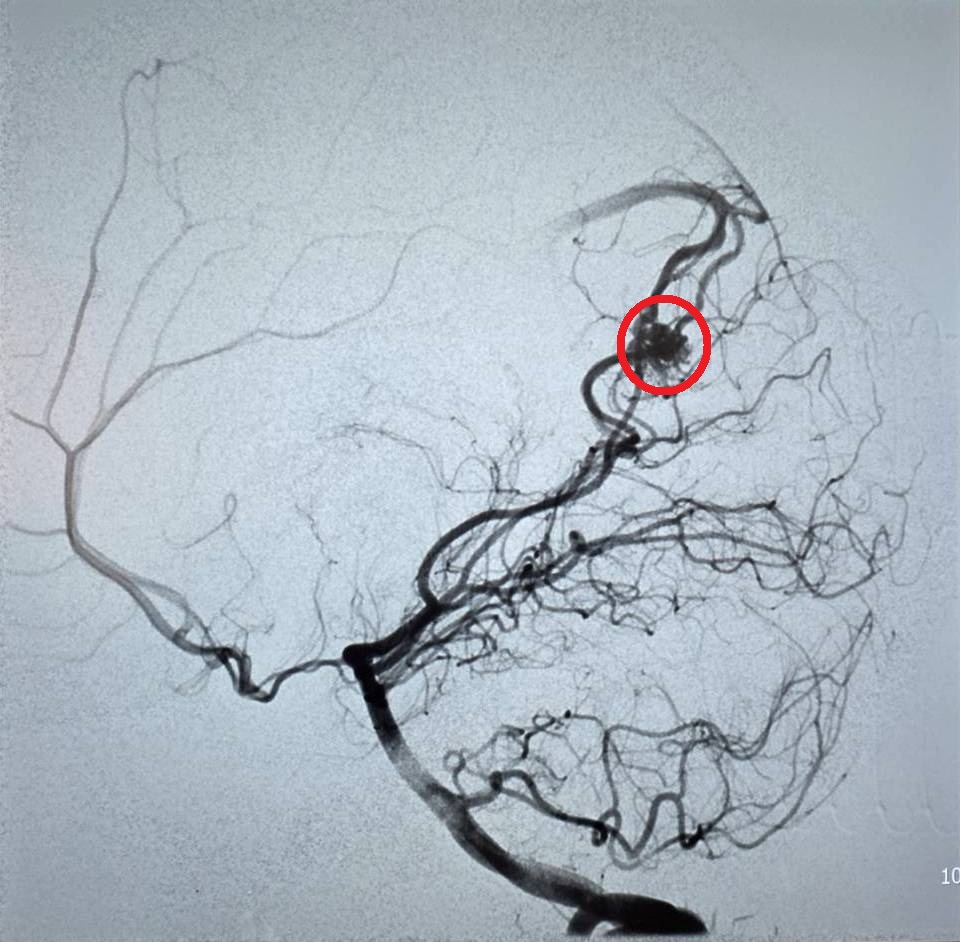

(特派員劉鳳瑩、陳明/苗栗報導)23歲的周小姐正值青春年華,日前卻在毫無預兆下感到一陣劇烈頭痛,隨即伴隨嚴重的頭暈與嘔吐感,家屬見狀趕緊將她送往大千綜合醫院急診。經腦部電腦斷層掃描,醫師赫然發現其左側腦部有出血跡象,且出血位置極其不尋常。醫療團隊隨即展開精密檢查,證實為罕見的「顱內動靜脈畸形」引發出血。所幸在神經放射科康靜維醫師及時進行微創血管內栓塞治療後,順利止住出血,病人症狀明顯改善,成功化解一場腦內危機。

康靜維醫師表示,顱內動靜脈畸形若未及時診斷與治療,每年約有1%至3%的出血風險。目前的治療技術已相當多元且成熟,主要包含:

1.微創血管內栓塞:透過導管進入血管,精準封堵畸形處。

2.立體定位放射治療:透過高能射線精準照射,使畸形血管萎縮。